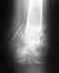

Уже прошло 5 мес. после операции. Должно было срастись, если все идет по плану.

Никакого мумия и кальция в лечении перелома костей голени применять не нужно. С местным остеопорозом делать ничего не нужно. Нужно ли сейчас что-то делать с фиксатором (динамизировать ли, в частности), можно сказать после знакомства со рентгенограммой, отражающей сегодняшнюю ситуацию, а не апрельскую.